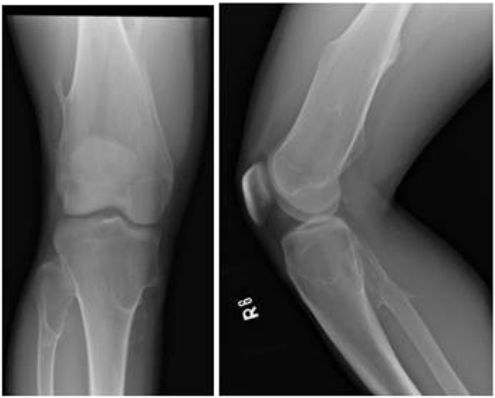

61.10歲男童從滑梯跌落以左膝著地,由於膝部疼痛腫脹,父母帶他來急診求診,並接受X光檢查,由此X光影像,顯示他發生了 何種的生長板傷害?

(A)Salter-Harris第一型(B)Salter-Harris第二型(C)Salter-Harris第三型(D)Salter-Harris第四型